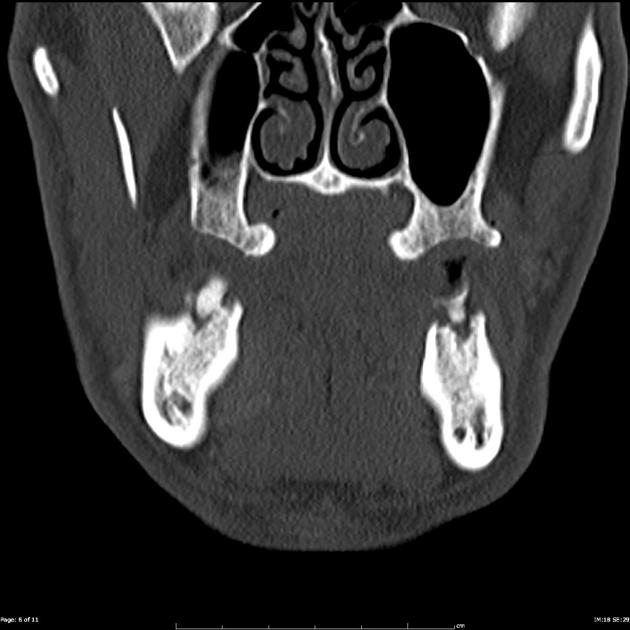

Tràn dịch khớp thái dương hàm (Temporomandibular joint effusion)